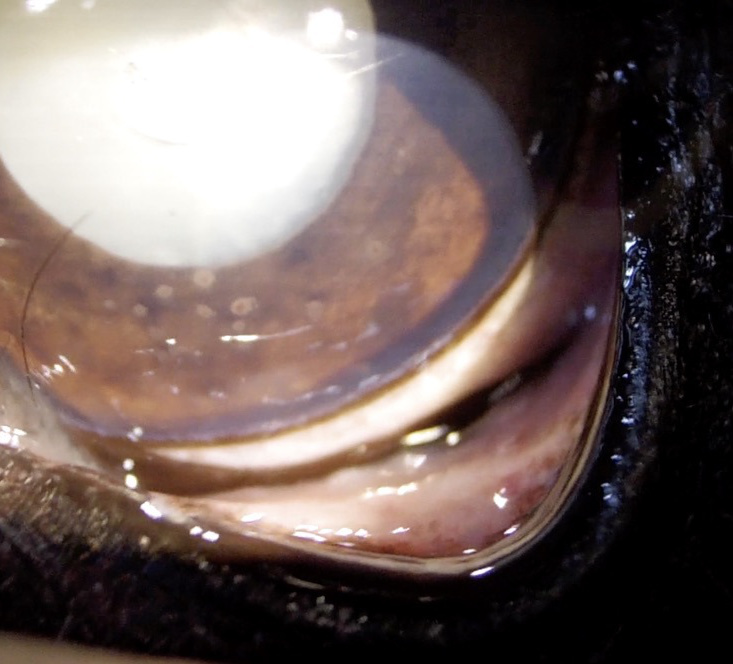

【超音波(エコー)検査】

目の中、特に硝子体や網膜など水晶体の裏側がどのような状態なのか調べます。エコー検査により、白内障の混濁状態や網膜剥離や眼内出血などの合併症の評価を行います。

犬 白内障

白内障(成熟)